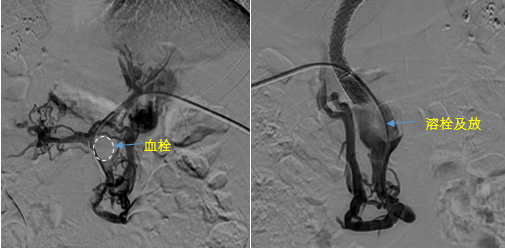

日前,西安國際醫(yī)學(xué)中心醫(yī)院消化病醫(yī)院為一位罕見巨大門靜脈血栓患者行TIPS手術(shù)。將患者體內(nèi)的“定時炸彈”拆除。9月份的一天,李女士晚飯后發(fā)覺惡心,嘔吐出鮮紅色的血塊,隨即又出現(xiàn)了黑便。在醫(yī)院檢查發(fā)現(xiàn)是食管胃底靜脈曲張破裂出血?!?/p>